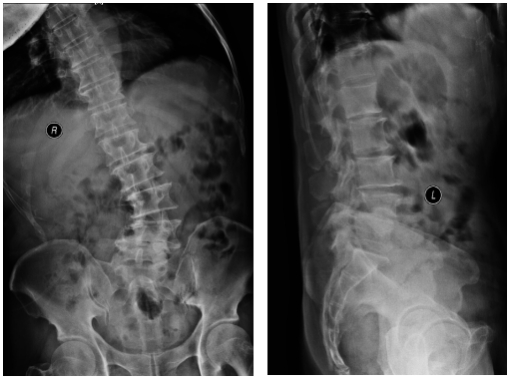

术前影像